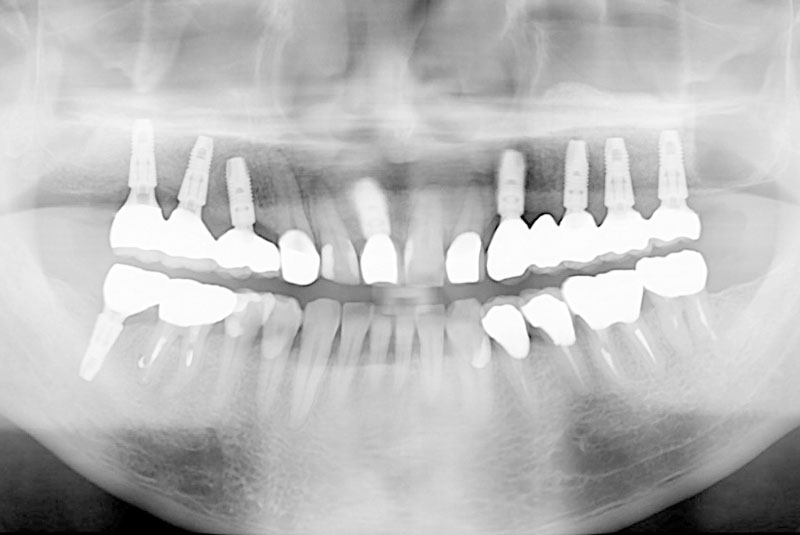

多数歯欠損のインプラント(サイナスリフト・GBR併用)

- 患者

- 50代男性

- 主訴

- インプラントができないかどうか相談。

できるだけきれいにしたい。

- 治療経過

- 前医にて上顎部分入れ歯を装着、下顎の奥歯を抜歯した状態で来院されました。また下顎の両側の臼歯の抜歯が必要と診断されたとのことでした。前医にインプラントを相談したが下顎はできるが、上顎は骨がないことを理由にインプラント不可能と診断され当院受診されました。診断の結果、下顎臼歯は保存可能、上顎臼歯部は左右上顎洞に対する骨造成(サイナスリフト)、前歯部はGBRにて骨造成を行い、インプラント埋入を行いました。

サイナスリフトはかなり専門性の高い外科処置であるため対応できる歯科医師は限られます。そのためショートインプラントや傾斜埋入で対応されることも多いですが、患者さんの年齢や希望を伺いながら当院では必要であれば積極的に行っております。その他不良補綴物の除去、根管治療、虫歯治療を行い全顎に対して審美的修復を行い治療終了までに2年を要しました。ちなみに当院では1本も抜歯は行いませんでした。保存できる歯と抜歯の必要な歯をしっかり診断することも必要です。

- 治療費

- インプラント検査 3万円

臼歯部インプラント(8本) 20万円×8

前歯部インプラント 22万円

サイナスリフト(左右) 20万円×2

GBR(前歯) 5万円

インプラント仮歯 10万円

アバットメント(9本) 7万円×9本

インプラント上部構造(フルジルコニアクラウン) 10万円×10本

インプラント上部構造(ジルコニアレイヤリングクラウン) 12万円

審美修復治療(フルジルコニアクラウン) 10万円×6本

根管治療 健康保険適応

コンポジットレジン修復 健康保険適応

計 509.3万円(税込み)

- 治療回数・期間

- 20回以上 治療期間 約2年